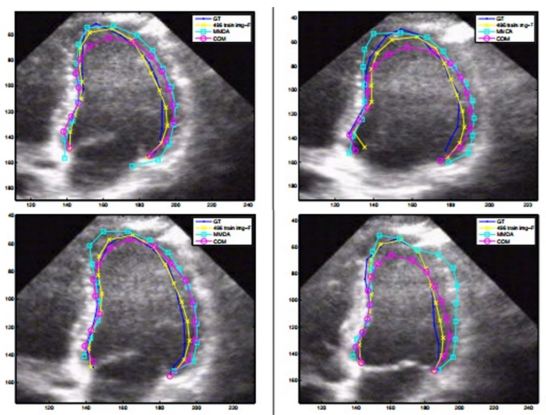

The two most important parameters to check the health of heart is ejection fraction measurement and assessment of the regional wall motion. These parameters can be obtained by the combination of segmentation and tracking of left ventricle (LV) endocardium from US scans of heart. Earlier attempts that were made to detect the size and contour using active shape and appearance model (32) but it had its own limitations. These models required a large annotated dataset for training, an initialization closer to local optimum, assumed a Gaussian distribution of shape and appearance from training samples which are not always accurate. Further, they did not consider priors which are important to capture all variations of wall motions. To resolve these issues, a new pattern recognition (40) approach for the problem of left ventricle tracking in US images is performed using DBN framework. The expected segmentation of the current time step t considers all previous segmentation contours c and current images produced. The author has defined current image I is a set of prior states where each state is defined by heart functions of systole and diastole i.e., and the contour c which defines the shape. In this respect, given the cardiac phase and contour, the shape model can be described probabilistically as:

where, denotes parameters of affine transformation, represents the cardiac phase and is the LV contour. Thus, to estimate contour segmentation and cardiac phase , the affine transformation has to be marginalized using the prior information estimated from the training dataset. A team of four cardiologists and one technician traced the left ventricle (LV) borders of 496 images dataset. The results were computed on 132 images. The traced images formed the GT of the experiment.

The model as described in Eq. 8 and Eq. 9, is implemented using two separate DBN-based architectures. The first is the rigid or affine classifier which provides the initial coarse contour shape of the LV. The second is the non-rigid classifier which produces estimated fine shape of LV. The rigid DBN-based system consists of three DBNs each trained on different priors (systole, diastole and non-LV). The discriminative training finds the maximum posterior (coarse contour) among each scale. The non-rigid classifier produces a fine contour of the LV using a principle component analysis (PCA) based shape model. Each of the DBN-based systems goes through training using predefined image datasets to train the hidden weights. Different performance parameters were computed such as Jaccard distance (JD), average error (AV), mean absolute distance (MAD) and average perpendicular error (AVP) from the predicted and GT contours. The average JD, AV, MAD and AVP were found to be 0.83, 0.91, 0.95 and 0.83 respectively. The corresponding object process model of the system is given in Figure 8. The resultant images are shown in Figure 9. The DBN-based method used limited size datasets to achieve better segmentation accuracy. The model showed effective tracking accuracy and less processing time compared to previous methods (41, 42). The prototype developed was encouraging but lacked higher accuracy and was demonstrated on a low data size.

Figure 8DBN based LV contour tracking model.